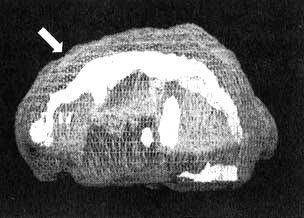

Трехмерное изображение — активный мозг, вид сбоку. Когда Расти находится под воздействием наркотиков, заметно возрастание активности в левой височной доле его мозга.

Трехмерное изображение — активный мозг, вид снизу. Обратите внимание на активную область в глубине левой височной доли мозга (отмечена стрелкой).